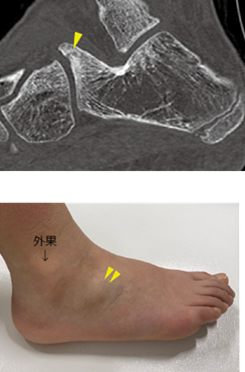

前方突起骨折について

踵骨前方突起骨折は二分靱帯の踵骨付着部の裂離骨折です。

上図:CT 下図:肉眼

(図21) MB Orthop. 38(5):55—64,2025大人とこどものスポーツ外来 下肢編【こども編】

小児アスリートの足関節・足部捻挫に対する外来診療 田中 博史 より抜粋

(図22) 関節外科 Vol.33 No.1(2014)81-87足部・足関節捻挫の治療 新鮮二分靱帯損傷ならびに足根洞周囲の靱帯損傷の 病態とスポーツ復帰までの治療 嶋 洋明 奥田龍三 より抜粋一部変更